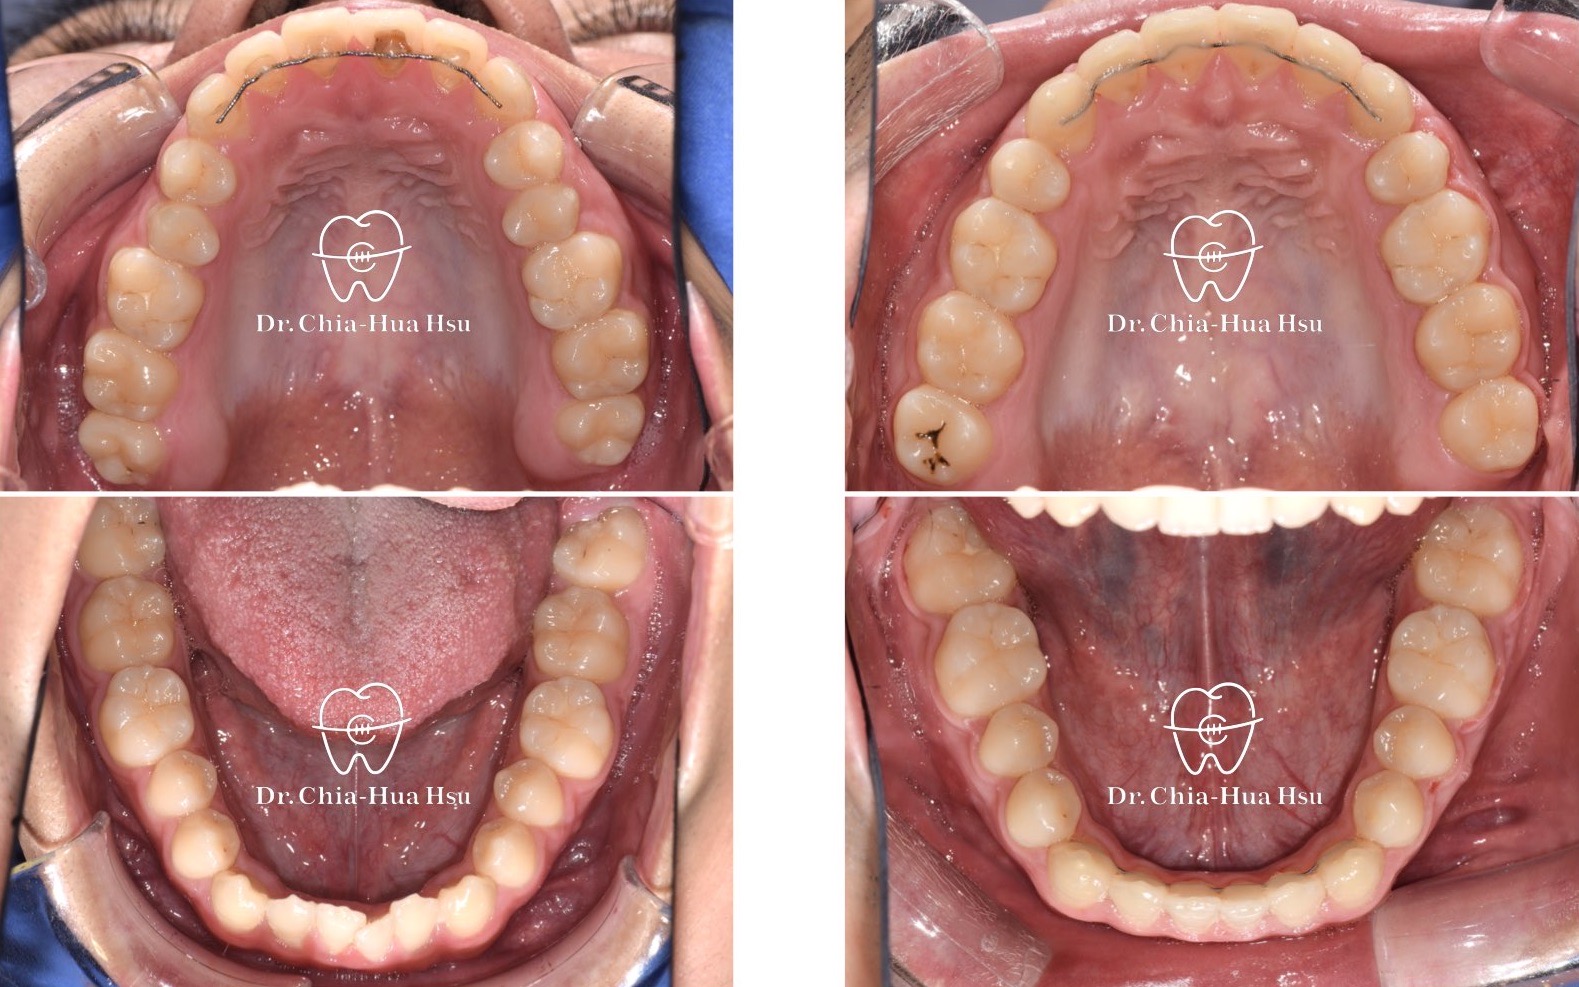

戽斗、開咬、齒列不正

成⼈矯正 | ⾦屬矯正 | 正顎⼿術 | 拔牙治療

• 20多歲的日籍大學生小時候有做過矯正治療,不過下顎骨隨著年紀持續生長,變成戽斗且開咬的樣子。於是,患者接受了矯正合併正顎手術,不但改善外觀,也改善了咬合功能與牙齒排列(患者很開心可以咬斷麵條)。

• 病患主訴:戽斗、前牙開咬。

• 問題分析:患者是標準的骨骼三類咬合(Skeletal Class III),下巴明顯較長,還有上顎牙弓過窄、開咬以及齒列不正。

• 治療方式:使用傳統金屬矯正器,合併正顎手術(雙顎),上顎拔除兩顆小臼齒以利手術方式進行上顎牙弓擴寬。

• 治療時間:1 年 7 個月。

• 治療結果:齒列排齊,咬合功能恢復,外觀更和諧。

治療前

治療後